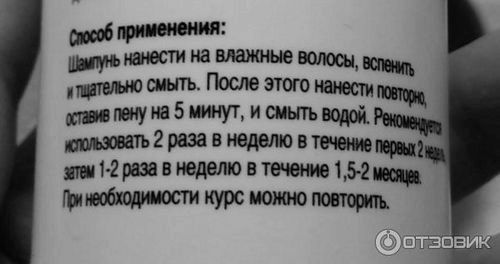

а так же спосіб застосування: